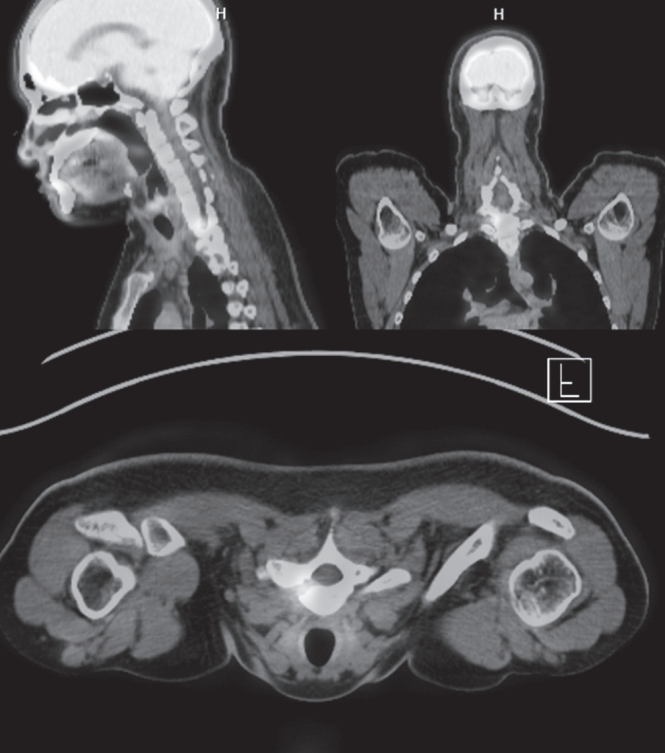

Targeted Resection of a T1 Pedicle Osteoid Osteoma Using O-Arm Navigation: A Minimally Invasive Approach to a Challenging Location

Osteoid osteoma is a benign bone-forming tumor that commonly affects young adults and often presents with severe nocturnal pain responsive to NSAIDs. While surgical resection is curative, lesions located in the spine, particularly near critical structures such as the vertebral artery and spinal cord, pose substantial diagnostic and surgical challenges. We report a case of a 24-year-old male with intractable night pain caused by an osteoid osteoma located at the superior margin of the right T1 pedicle. Despite extended NSAID therapy, the patient’s symptoms persisted. Multimodal imaging including MRI, CT, and PET-CT confirmed the diagnosis and revealed the lesion’s proximity to vital neurovascular structures. To minimize morbidity, we employed intraoperative O-arm navigation integrated with preoperative imaging to achieve precise localization and targeted resection through a limited posterior approach. The nidus was successfully excised en bloc without complications. Postoperatively, the patient experienced immediate pain relief and returned to normal activities within days. This case highlights the utility of real-time 3D navigation in managing spinal osteoid osteomas and supports its use as a safe, effective alternative to traditional wide exposure techniques, particularly in anatomically constrained regions of the spine.